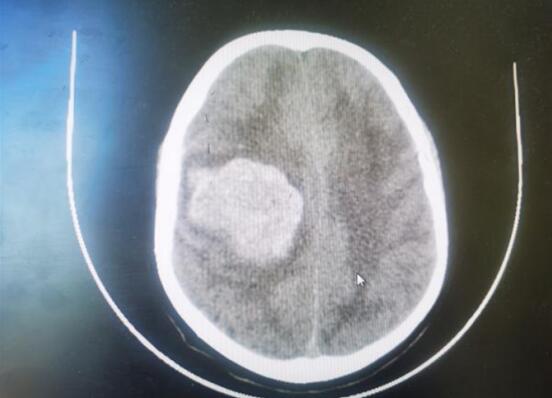

近日,一例56歲大量腦出血的中年患者,在江寧中醫(yī)院得到成功救治?;颊咄话l(fā)暈倒,急查頭顱CT顯示:顱內(nèi)出血約70ml,既往有口服“阿司匹林”用藥史,神經(jīng)外科醫(yī)生在權(quán)衡利弊后,決定予以開顱血腫清除+去骨瓣減壓術。醫(yī)生們與死神賽跑,經(jīng)過4個小時的手術,術后第二天患者蘇醒。

術前CT